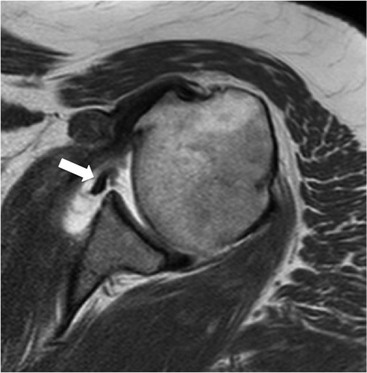

Anterior GHJ dislocation causes tearing and detachment of the anteroinferior glenoid labrum, known as a Bankart lesion. The location of the labral tear is described according to clockface terminology: 12 o'clock represents the biceps anchor, and 3 o'clock is anterior at the equator of the glenoid. Fluid signal intensity or contrast medium extending between the glenoid and labrum is the primary sign of a labral tear (Fig. 46-9). The labrum may become displaced, and it is important to assess the position of the labrum with respect to the face of the glenoid.

More severe injury may be associated with a bony injury of the glenoid rim, usually called a bony Bankart lesion (Fig. 46-10). Non-enhanced CT may occasionally be preferred to assess the size of the bony defect of the glenoid. There is usually associated impaction injury on the posterosuperior aspect of the humeral head called a Hill–Sachs defect (Figs. 46-11 and 46-12).